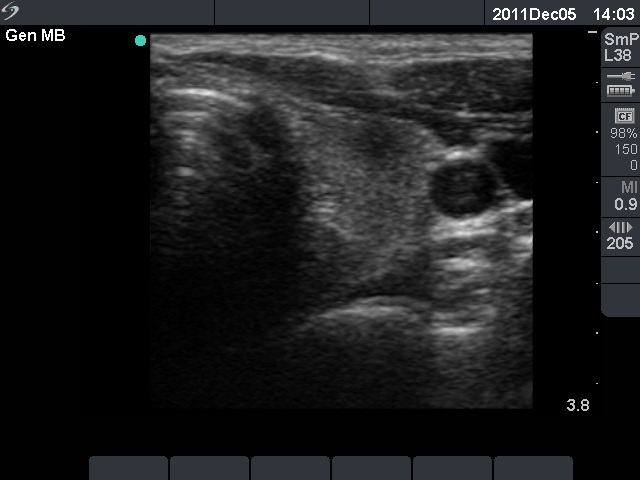

The ultrasound pattern of de Quervain's thyroiditis and that of papillary cancer are very similar: a hypoechogenic lesion with blurred borders are found in both cases. They differ in vascularization statistically but the vascular pattern has only limited practical significance. In the acute phase of de Quervain's thyroiditis the vascularization is generally decreased but even in this case the situation was the opposite. The finding of not one but multiple hypoechogenic areas favored the possibility of subacute thyroiditis.

The relapse of de Quervain's thyroiditis in the contralateral lobe is a very frequent finding but not one year after the appearance of the disease. We supposed that the immunological changes during and after pregnancy explained the relatively late relapse of the disease.